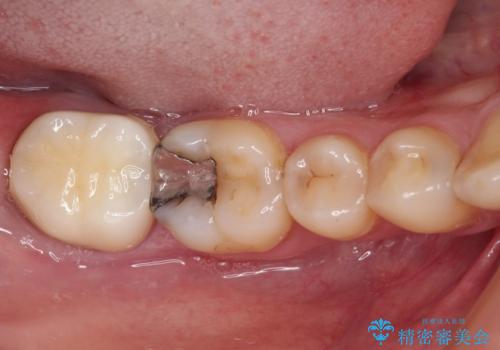

- 右上下の奥歯がむし歯でしみたり痛んだりするとのことで来院された患者様です。

下顎の奥歯は強い痛みを感じており、既に歯髄に不可逆的な炎症が起きていると診断されたため、根管治療の後にセラミッククラウンにて補綴治療を行うこととしました。

下顎のむし歯は歯肉の中にまで及んでいたため、一部歯槽骨を削除し、歯肉縁上に健全歯質が位置するよう外科処置を併用しました。